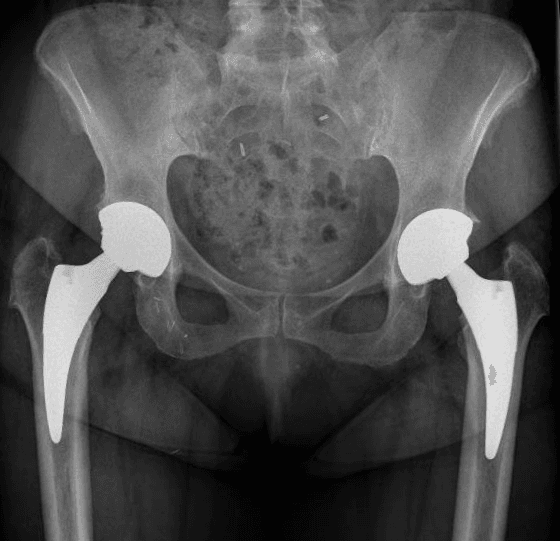

L’intervento di artroprotesi d’anca prevede la sostituzione dell’articolazione dell’anca mediante l’impianto di componenti protesiche in leghe metalliche, come il titanio, accoppiati a materiali plastici (polietilene di ultima generazione) e/o ceramiche. Questo processo include la sostituzione del femore prossimale (testa e collo) e il rivestimento della cavità acetabolare del bacino. L’obiettivo principale di questa procedura è ripristinare un’articolazione stabile e funzionale, migliorando significativamente la capacità di movimento del paziente, alleviando il dolore e migliorando la qualità della vita.

Esistono diverse vie d’accesso chirurgiche per l’artroplastica d’anca; quelle preferite nel nostro centro, a seconda delle caratteristiche del paziente, sono la via postero-laterale e la via anteriore. Ognuna di queste vie ha caratteristiche e vantaggi specifici, e la scelta è sempre basata sulle esigenze individuali del paziente.